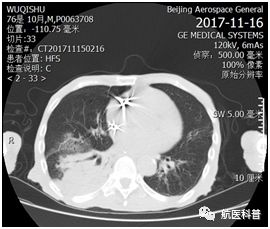

其中(zhong)一(yi)患者爲(wei)73歲男性,因“髮(fa)熱伴咳嗽1天餘”2017年(nian)11月15日(ri)入院,體(ti)重(zhong) 40kg、高(gao)1.65m、BMI 14.7kg/m2,患者1天餘前(qian)着涼後(hou)出現(xian)咳嗽、咳痰,爲(wei)黃色粘痰,伴髮(fa)熱,最高(gao)體(ti)溫37.5攝氏度,既往帕金森病史10年(nian),胃潰瘍行胃大(da)部(bu)切除術(shù)30年(nian),近2月體(ti)重(zhong)下降10公(gōng)斤,入院查體(ti)雙肺可(kě)聞及(ji)彌漫痰鳴音,白蛋白26g/L,聯(lian)係(xi)影像科(ke)緊急完善(shan)肺部(bu)CT可(kě)見右肺大(da)面積實變。